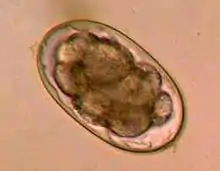

| Egg of Ancylostoma sp. | |